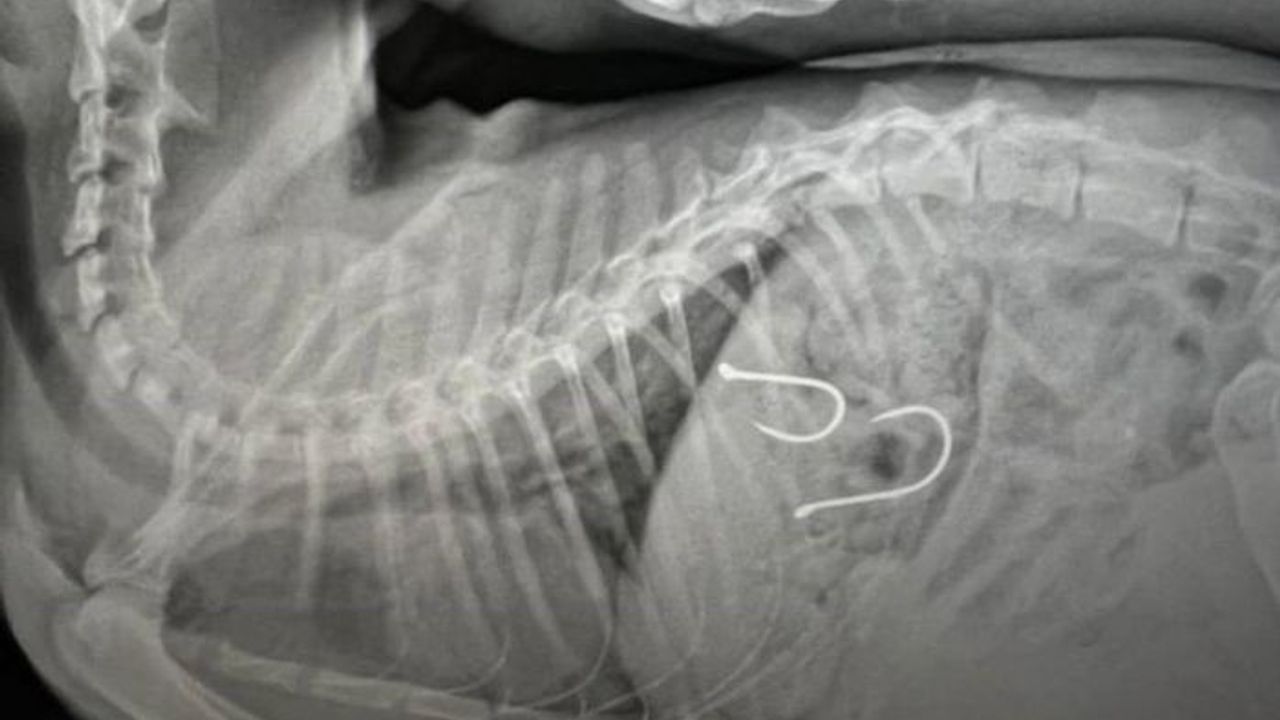

Gelen ihbar üzerine kedi, ekipler tarafından müşahede altına alınmış ve sağlık durumu kritik olan yaralı hayvana acil olarak müdahale edilmişti. Çekilen röntgen sonucunda olta iğnelerinin kedinin midesine saplandığı anlaşılmış ve sonrasında ise kedi ameliyata alınmıştı.

Kedinin sağlık durumu ile ilgili Balıkesir Büyükşehir Belediyesi Sokak Hayvanları Tedavi Merkezi'nden edinilen son bilgilere göre, 2 adet olta iğnesi ve misinasının kedinin midesinden başarılı bir operasyonla çıkarıldığı, olta kancasının enfeksiyon oluşturma riskine karşı, antibiyotik ve serum tedavisine başlandığı belirtildi. Kedinin genel sağlık durumunda şu an için bir olumsuzluğun söz konusu olmadığı ve 48 saat yoğun bakımda tutulacağı aktarıldı.